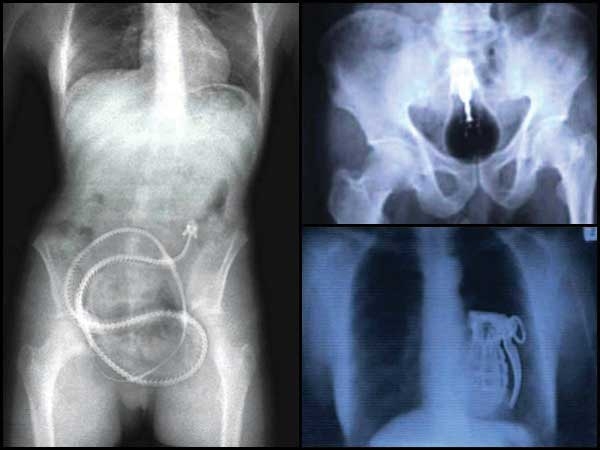

ಅಚ್ಚರಿಯ ಜಗತ್ತು: ಇವರು ಕೈಗೆ ಸಿಕ್ಕಿದನ್ನೆಲ್ಲಾ ತಿಂದು ಬಿಡುತ್ತಾರೆ!

ಆಡು ಮುಟ್ಟದ ಸೊಪ್ಪಿಲ್ಲ ಎನ್ನುವುದೊಂದು ಗಾದೆ. ವಾಸ್ತವವಾಗಿ ಮನುಷ್ಯರು ತಿನ್ನುವ ಆಹಾರವಸ್ತುಗಳನ್ನು ಪಟ್ಟಿ ಮಾಡಿದರೆ ಆಡು ಸಹಾ ನಾಚಿಕೆಪಟ್ಟು ಓಡಿಹೋಗಬೇಕು, ಅಷ್ಟಿವೆ. ಸೊಪ್ಪುಗಳು, ಮರದ ಚೆಕ್ಕೆ, ಮೊಗ್ಗು, ಹೂವು, ಬೇರು, ಹಣ್ಣು, ಹಣ್ಣಿನ ಸಿಪ್ಪೆ, ಗೊರಟು, ಏಕದಳ,ದ್ವಿದಳ ಧಾನ್ಯಗಳು, ತರಕಾರಿಗಳು, ಎಣ್ಣೆ ಇತ್ಯಾದಿಗಳೆಲ್ಲಾ ಸಸ್ಯಜನ್ಯವಾದರೆ ವಿವಿಧ ಪ್ರಾಣಿಗಳ ಮಾಂಸ ಮತ್ತು ಇತರ ಭಾಗಗಳನ್ನೂ ಮನುಷ್ಯರು ಆಹಾರರೂಪದಲ್ಲಿ ಸೇವಿಸುತ್ತಾ ಬಂದಿದ್ದಾರೆ. ಅಷ್ಟೇ ಏಕೆ, ವಿಷವೆಂದು ತಿಳಿದರೂ ಆಹಾರದ ಮೂಲಕ, ನರಕ್ಕೆ ಚುಚ್ಚಿಕೊಳ್ಳುವ ಇಂಜೆಕ್ಷನ್ ಮೂಲಕ ಸೇವಿಸಿ ವ್ಯಸನಿಗಳಾಗುತ್ತಾರೆ.

ಆದರೆ ನಮ್ಮ ಜಗತ್ತಿನಲ್ಲಿ ಕೆಲವು ಭಯಂಕರರಿದ್ದಾರೆ. ಇವರು ನಾವು ಯಾರೂ ಊಹಿಸದ, ಬಾಯಿಗಿಟ್ಟುಕೊಳ್ಳಲೂ ಅಸಹ್ಯಪಡುವ ವಸ್ತು, ಕ್ರಿಮಿ, ಜೀವಿಗಳನ್ನು ಕರಕರನೇ ಅಗಿದು ನುಂಗುತ್ತಾರೆ. ಈ ಪರಿ ನೋಡಿದರೆ ಈ ಹುಚ್ಚರು ನಿಜವಾಗಿಯೂ ಮನುಷ್ಯರೇ ಅಥವಾ ಮನುಷ್ಯರೂಪ ಧರಿಸಿದ ಅನ್ಯಗ್ರಹಜೀವಿಗಳೇ ಎಂಬ ಅನುಮಾನ ಮೂಡುತ್ತದೆ.

ಇಂತಹ ರೋಚಕವಾದ ಪ್ರಕರಣಗಳನ್ನು ಕೆಳಗಿನ ಸ್ಲೈಡ್ ಶೋ ಮೂಲಕ ಪ್ರಸ್ತುತಪಡಿಸಲು ಬೋಲ್ಡ್ ಸ್ಕೈ ತಂಡ ಹರ್ಷಿಸುತ್ತದೆ. ಓದುಗರಲ್ಲಿ ಎಚ್ಚರಿಸುವುದೇನೆಂದರೆ ಇವುಗಳಲ್ಲಿ ಯಾವುದೇ ಕ್ರಮವನ್ನು ದಯವಿಟ್ಟು ಅನುಸರಿಸಲು ಹೋಗಲೇಬೇಡಿ. ಕೆಲವು ಪ್ರಕರಣಗಳು ಬೇಕೆಂದೇ ಜನರು ಸೇವಿಸುತ್ತಿದ್ದರೆ ಇನ್ನುಳಿದವು ಆಕಸ್ಮಿಕವಾಗಿ ಹೊಟ್ಟೆಯಲ್ಲಿ ಸಿಕ್ಕಂತಹವು. ಇವುಗಳಲ್ಲಿ ಬ್ಯಾಟರಿ, ಗಾಜಿನ ಚೂರು ಮೊದಲಾದವುಗಳೆಲ್ಲಾ ಸೇರಿವೆ. ಈ ಬಗ್ಗೆ ನಿಮಗೆ ಏನಿನಿಸಿತು ಎಂಬುದನ್ನು ನಮಗೆ ಖಂಡಿತಾ ತಿಳಿಸಿ, ಇದಕ್ಕಾಗಿ ಕೆಳಗಿನ ಕಮೆಂಟ್ಸ್ ಭಾಗವನ್ನು ಬಳಸಿಕೊಳ್ಳಿ...

ಕೈಬಾಂಬು (Hand Grenade)

ರಾಜೀವ್ ಗಾಂಧಿಯವರನ್ನು ಹತ್ಯೆಮಾಡಿದ ಆತ್ಮಹತ್ಯಾದಳದಂತಹ ಪಂಗಡಕ್ಕೆ ಸೇರಿದ್ದ ತಿಳಿಗೇಡಿಯೊಬ್ಬನಿಗೆ ಜನನಿಬಿಡ ಸ್ಥಳಕ್ಕೆ ಸುರಕ್ಷಾ ಸಿಬ್ಬಂದಿಯ ಕಣ್ಣು ತಪ್ಪಿಸಿ ಕೈಬಾಂಬೊಂದನ್ನು ಕೊಂಡುಹೋಗುವ ವಿಚಾರ ಹೊಳೆಯಿತು. ಅದೇ ಕೈಬಾಂಬನ್ನು ನುಂಗಿಕೊಂಡು ಹೋಗುವುದು. ಅಂತೆಯೇ ನುಂಗಿಯೇಬಿಟ್ಟ. ಮುಂದಿನ ಸ್ಲೈಡ್ ಕ್ಲಿಕ್ ಮಾಡಿ

ಆದರೆ ಇದನ್ನು ಸ್ಟೋಟಿಸಲು ಇದರ ಪಿನ್ ಎಳೆಯುವುದು ಹೇಗೆ? ಇದರ ಬಗ್ಗೆ ತಲೆಕೆಡಿಸಿಕೊಳ್ಳುತ್ತಿದ್ದಾಗಲೇ ಸುರಕ್ಷಾ ದಳದವರ ಕೈಗೆ ಸಿಕ್ಕಿಬಿದ್ದು ಬಳಿಕ ತಪಾಸಣೆಯಲ್ಲಿ ಹೊಟ್ಟೆಯಲ್ಲಿ ಕೈಬಾಂಬ್ ಇದ್ದುದು ಪತ್ತೆಯಾಯಿತು. ಬಳಿಕ ಇದನ್ನು ಶಸ್ತ್ರಕ್ರಿಯೆಯಿಂದ ಹೊರತೆಗೆಯಲಾಯಿತು.

ಮಾದಕ ಪದಾರ್ಥಗಳನ್ನು ಕಳ್ಳಸಾಗಣೆ ಮಾಡುವ ಸಾಮಾನ್ಯವಾದ ಈ ವಿಧಾನದಲ್ಲಿ ಹೊಟ್ಟೆಯಲ್ಲಿ ಕರಗಲಾರದ ರಬ್ಬರಿನಂತಹ ವಸ್ತುವಿನಿಂದ ಚಿಕ್ಕ ಕ್ಯಾಪ್ಯೂಲುಗಳನ್ನು ತಯಾರಿಸಿ ಇದರಲ್ಲಿ ಮಾದಕ ಪದಾರ್ಥ ತುಂಬಿ ನುಂಗಿ ಬಿಡುತ್ತಾರೆ. ವಿಮಾನದ ಪ್ರಯಾಣದ ಬಳಿಕ ಬಹಿರ್ದೆಶೆಯಲ್ಲಿ ಜೀರ್ಣಗೊಳ್ಳದೇ ಹೊರಬಂದ ಈ ಗುಳಿಗೆಗಳನ್ನು ಮತ್ತೆ ಸಂಗ್ರಹಿಸುತ್ತಾರೆ. ಮಲೇಶ್ಯಾದಲ್ಲಿ ಇದೇ ವಿಧಾನವನ್ನು ಅನುಸರಿಸಿ methamphetamine ಎಂಬ ಮಾದಕ ಪದಾರ್ಥವನ್ನು ಕಳ್ಳಸಾಗಣೆಗೊಳಿಸಲು ಯತ್ನಿಸುತ್ತಿದ್ದ ನೈಜೀರಿಯಾದ ನಾಗರಿಕರೊಬ್ಬರನ್ನು ಬಂಧಿಸಿ ಅವರಿಂದ 52 ಗುಳಿಗೆಗಳನ್ನು ಸಂಗ್ರಹಿಲಾಯಿತು.